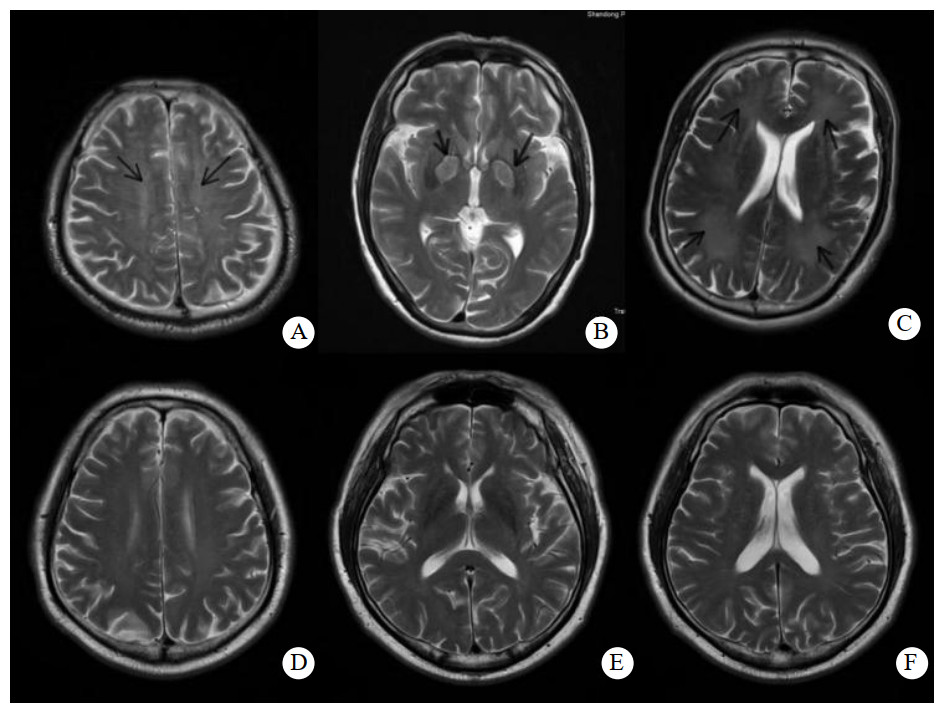

常规MRI中DEACMP表现为长T1、T2信号。DWI中DEACMP组与ACOP组相比,病变区域信号增强。见图 1。

| A为DEACMP半卵圆中心高信号改变;B为DEACMP苍白球高信号改变;C为DEACMP侧脑室周围高信号改变;D为Non-DEACMP组半卵圆中心低信号;E为Non-DEACMP组苍白球低信号;F为Non-DEACMP组侧脑室周围低信号 图 1 DEACMP组和ACOP组不同部位在ADC图中的表现 Fig 1 ADC images of different parts in DEACMP group and ACOP group |

影像学研究显示,CO中毒后脑组织缺血、缺氧,导致神经细胞膜钠钾离子泵功能障碍,细胞内外水分子扩散异常,细胞外水分子向细胞内移动后造成细胞毒性水肿,使组织内水分子布朗运动的限制性增大,从而出现ADC值降低和DWI上信号相对升高。研究表明,在病变区DWI未出现信号异常之前就可以测得ADC值不同程度下降,在早期缺血的检测上ADC值更为敏感。ADC值减小越多,迟发性脑病发生的可能性越大,二者存在着相关性。ADC值降低对DEACMP诊断具有重要价值[15]。本研究显示,颅脑MRI半卵圆中心ADC值与DEACMP发病相关,经ROC评价发现,CRP与ADC联合在预测DEACMP的诊断效能方面的特异度和敏感度优于颅脑MRI半卵圆中心。但ACOP和DEACMP的发病率较低,可通过继续扩大样本量后再评价其预测价值。